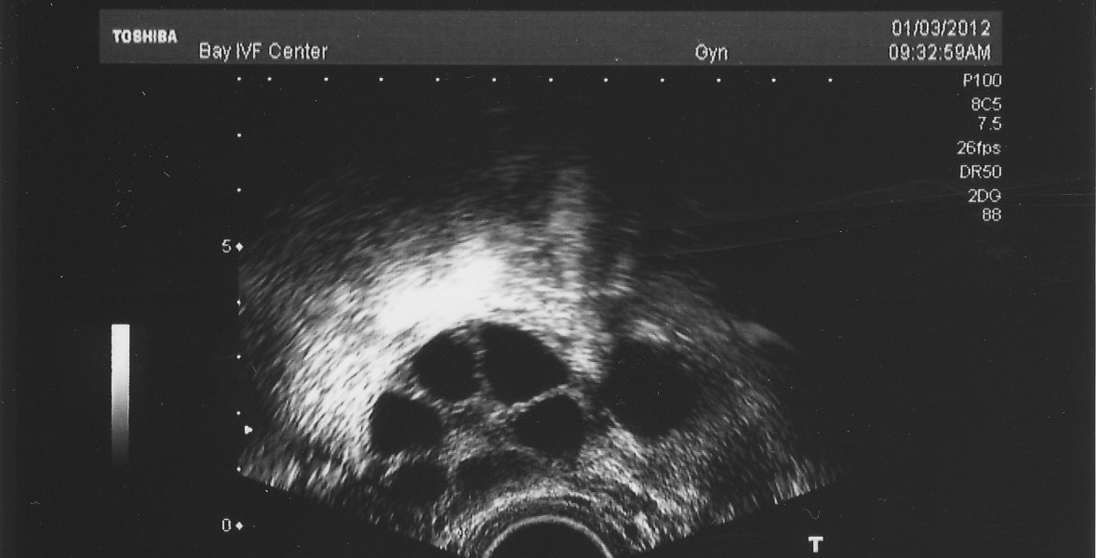

During IVF, your doctor uses ultrasounds and blood tests to track your follicles. They’re not just counting—they’re strategizing. Here’s how it works:

- Baseline Check: Before meds, they see how many antral follicles (resting ones) you’ve got.

- Stimulation Phase: Meds like FSH (follicle-stimulating hormone) kick things into gear, and they watch growth daily.

- Trigger Time: When most follicles hit 16-20 mm, they give you a “trigger shot” to ripen the eggs.

- Size Matters: 16-20 mm is the gold standard for maturity.

- Even Growth: A mix of big and small is okay, but they want a few leaders.

- Hormone Levels: Estrogen should rise with follicle count—too low or high can signal trouble.

Here’s a shocker: not every follicle has an egg! On average:

- 70-80% of mature follicles yield an egg.

- So, 10 follicles might mean 7-8 eggs, not 10.